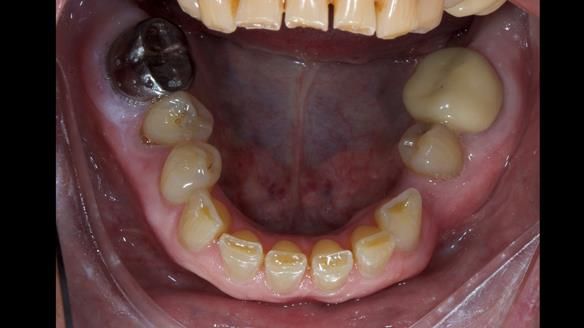

This is one of those cases that reminds me why I love removable prosthodontics. Pam was an absolute joy to treat — we were on the same page throughout. Her old upper flexible denture was loose, uncomfortable, and unaesthetic. We replaced it with a carefully designed metal-based upper partial denture/splint and new porcelain-bonded-to-zirconia (PBZ) crowns for the canines. The result is stable, comfortable, and natural-looking.

- Diagnosis and plan – Flexible upper denture ill-fitting with poor stability, retention, and appearance. Plan: metal-based upper partial denture/splint with lighter porcelain-bonded-to-zirconia crowns on UR3 and UL3.

The result

- Better support for lips and lower face.

- Natural smile and improved chewing.

- Designed to protect remaining teeth.

- Future additions possible if needed.